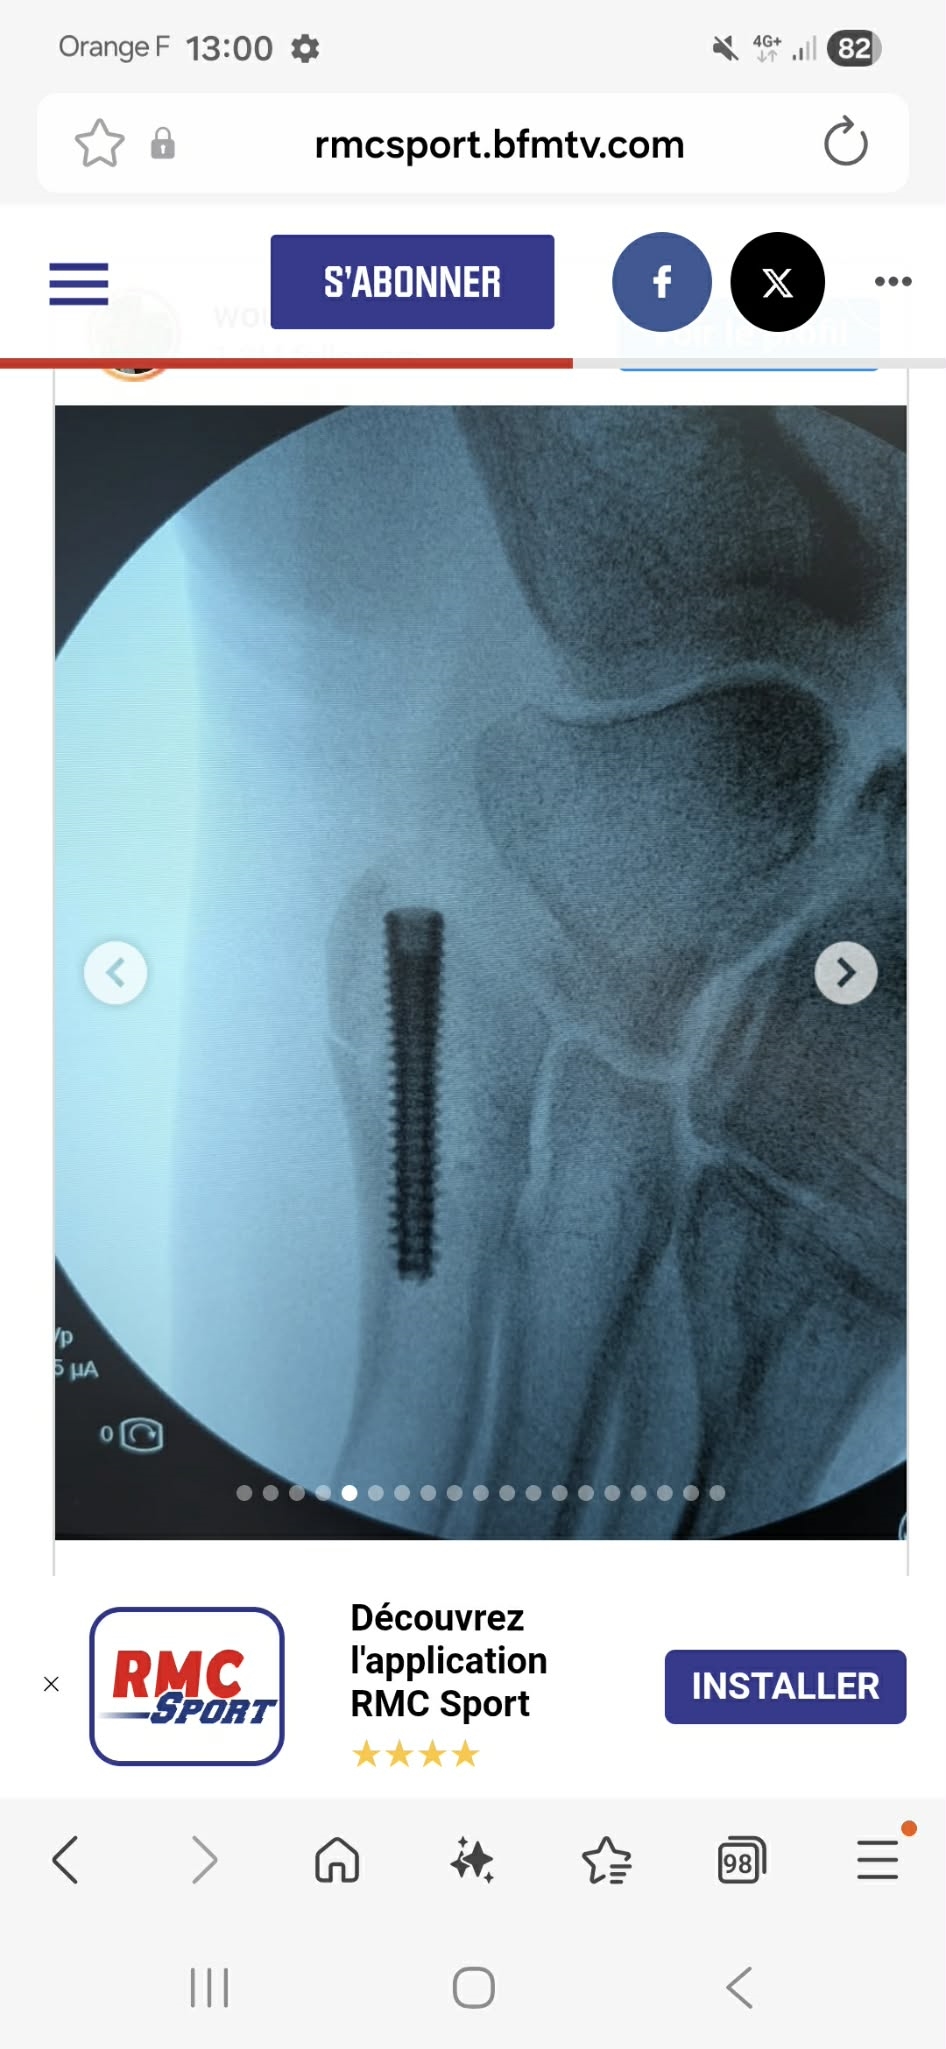

rody83 No pain, no gain | En effet, pas grand chose à voir avec la cheville... d'ailleurs ça me rappelle (toutes proportions gardées, dans mon cas c'était un membre supérieur) ce que je suis fait à la main y'a un an (= broche dans la tête de M5). Par contre il y a fort à parier qu'il lui faudra repasser sur le billard pour enlever la vis... avec une petite indispo associée. Message édité par rody83 le 13-01-2026 à 15:05:06 --------------- .: Passions | Galerie | Blog :. |